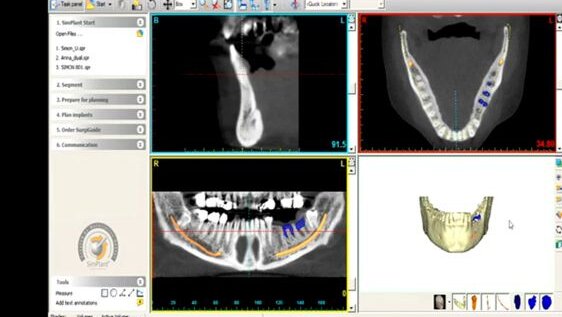

Materialise Dental est leader sur le marché de la dentisterie implantaire guidée par ordinateur. Sa technologie SimPlant existe depuis près de deux décennies, et fournit un outil totalement intégré de planification de traitement implantaire. SimPlant a été conçu pour être convivial et facile à travailler. Il guide les professionnels dentaires, étape par étape, au cours de leur planification implantaire et leur permet de planifier un cas d'implant avec facilité et confiance. La planification en 3D aide les cliniciens à obtenir des résultats esthétiques élevés, et de communiquer d'une manière visuelle transparente pour toutes les parties concernées.

La solution SurgiGuide Dental SAFE de Materialise est utilisée avec un kit spécifique de chirurgie guidée. Il fournit des conseils de forage, la pose guidée de l'implant et le contrôle total de la profondeur. Utilisé en conjonction avec le logiciel de planification implantaire SimPlant, SAFE SurgiGuide propose un outil convivial pour augmenter la précision et la prévisibilité dans la chirurgie implantaire. Zimmer Dental propose désormais à ses clients la possibilité de planifier leurs opérations avec SimPlant et la chirurgie guidée avec l'instrumentation de chirurgie guidée compatible Zimmer.

Materialise Dental a établi la norme pour adapter le service aux besoins de ses clients à travers le développement de la notion CompatAbility SimPlant, incluant les logiciels SimPlant et une gamme de guides de forage SurgiGuide facile à sélectionner. Suivant les types de soutien SurgiGuide (os, muqueuse et guides de forage SurgiGuide dento-portés), Materialise Dental propose également des solutions adaptées au cas SurgiGuide: SAFE (utilisé avec un kit spécifique de chirurgie guidée), Universal (utilisé avec un kit chirurgie de chirurgie guidée) et Pilot (offrant une orientation des forets pilotes).

Le concept CompatAbility , ouvert et complet, de SimPlant offre aux utilisateurs du monde entier des solutions bien documentées qui sont compatibles avec toutes les marques d'implants et toutes les images CT et contribue à accroître la précision, l'esthétique améliorée, la chirurgie mini-invasive et immédiate Smile.